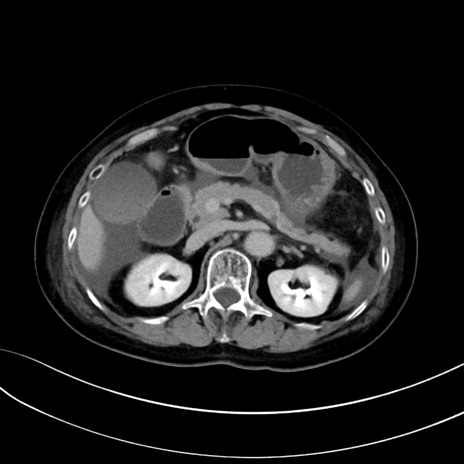

症例13 CT(横断像)1日半後